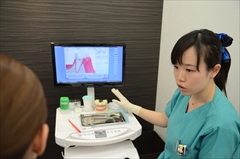

まずは、顕微鏡検査により、お口の細菌の種類や数などを調べ検査します。

次に、その細菌に合うお薬を服用して除菌していきます。

そして、その細菌に合う歯みがき粉を日々のケアに使って除菌していきます。

このような過程を踏んで、お口の中をきれいに除菌していくので、治療効果を得やすくなります。